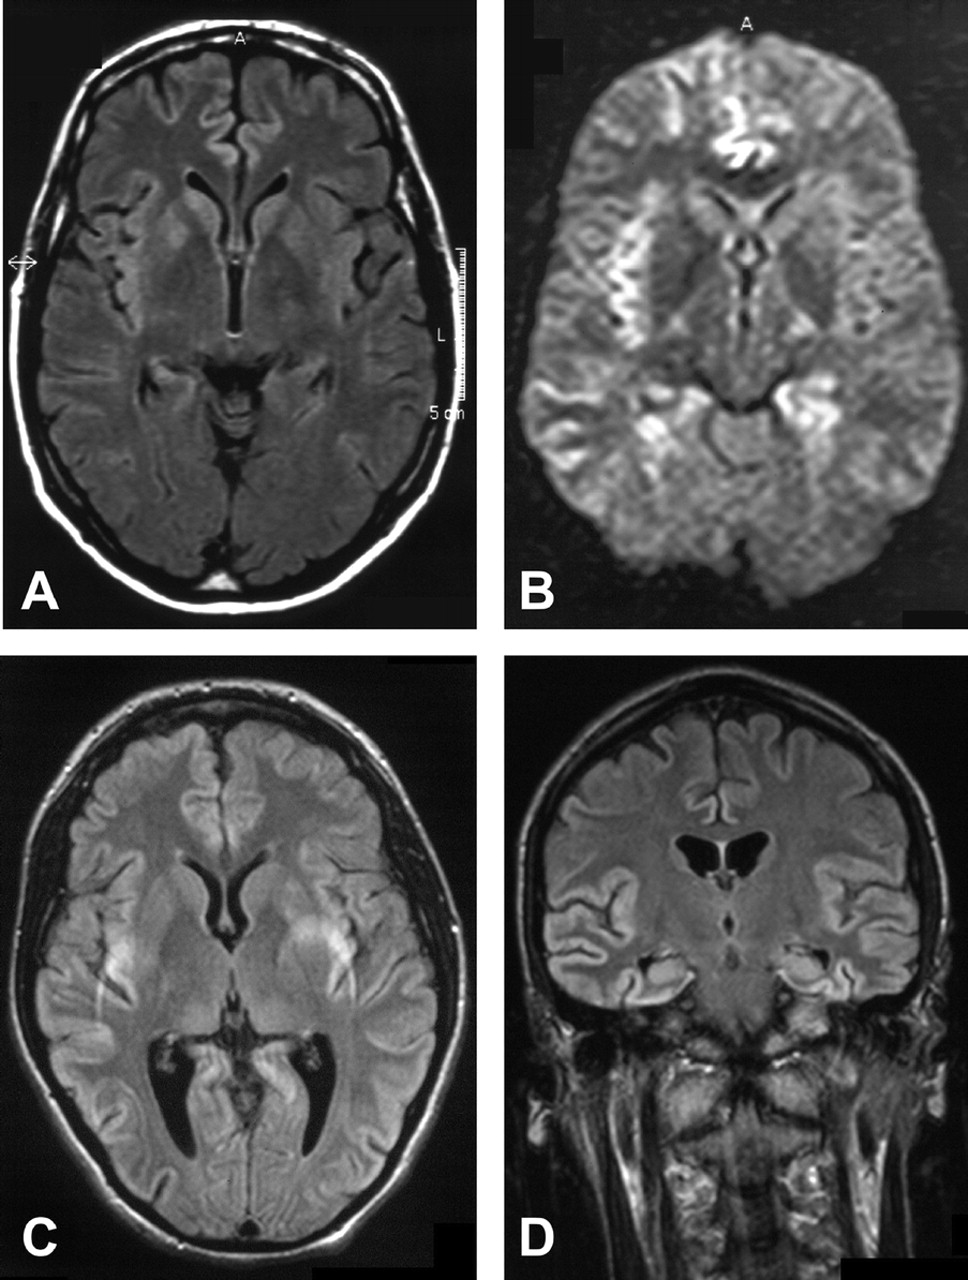

我们评估了天赋和T2图像7的9个病人。一个醉酒驾车和一个质子density-weighted形象(PD)除了可用(表2和图1中,通过D)。除了一个病人(例3)检查后整体疾病持续时间的三分之一。所有七个病人显示皮层信号增加,而只有两个病人显示hyperintense基底神经节。受影响的大脑区域通常是颞叶(所有的病人),脑岛和海马体(6例),其次是额叶、顶叶、枕叶和扣带回(5例)。病人呈现焦迹象,相应的MRI大脑区域受到影响:额叶是显示失用症和失语症患者的影响,在病人显示hypacusis颞叶,枕叶视觉障碍患者。

下面的案例报告是选择来说明一个典型的MRI显示信号增加大脑皮层区域在一个案例中(8例)和SPECT异常在另一个(例4)。

他住院两个月后出现症状。核磁共振成像显示信号增加额叶和颞叶T2。天赋还显示一个信号增加parieto-occipital叶和海马。开始三个月后,病人被送去精神病院,因为他行为异常发达,成为害怕电。四个月后开始,他的神经状态仍然是正常的,除了抑制眉间反射和轻度痴呆(21 30分的细微精神状态检查)。当时MRI显示更少的参与fronto-parieto-occipital叶但轻微的信号变化的基底神经节(右尾状核头在左边)(见图1一个)。SPECT显示低灌注的左颞叶。但是没有PSWCs脑电图显示间歇性theta-delta活动。病人在疾病发作10个月后死亡。

增加核磁共振信号中检测出所有VV1患者的皮层区域。在文献中,大脑皮层信号增加据报道在单一VV1案例报告。在我们的案例中,颞叶皮层的影响通常7例(7),其次是海马和脑岛(6 7例,每个)。

信号增加海马没有被描述为一个典型的发现在sCJD和只有两次。21日,22日频繁出现的异常在我们VV1病例表明,它可能是一个特定功能的罕见的库贾氏症亚型。

基底神经节作为典型的MRI信号改变已报告发现63%的sCJD病例(包括只有t2加权核磁共振成像)。19然而,只有两个七VV1患者显示异常。在一个案例中,这些变化是t2加权图像上可见发病后4个月。其他病人显示只有轻微的信号增加右尾状(相对于左尾状)在第一次扫描开始3个月后(T2,天赋)和更突出的一分之一FLAIR-weighted随访检查开始后3.5个月。少见的原因的基底神经节信号异常可能是diffusion-weighted图像,最敏感的技术,只是在我们的一个情况下使用。23